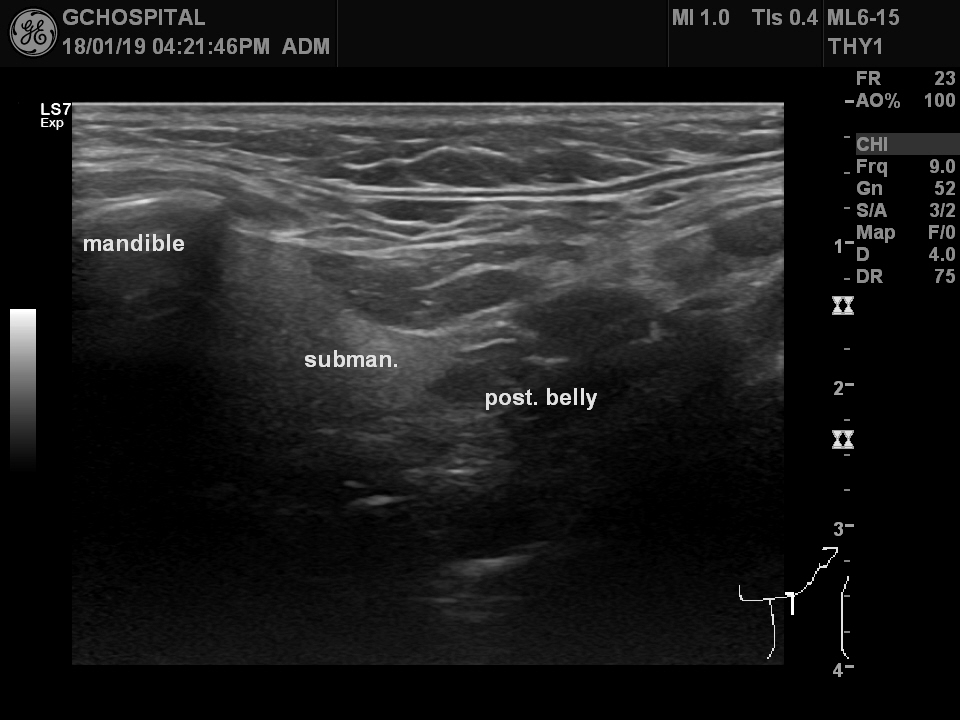

US20180119162155_US_NO_20180119_002